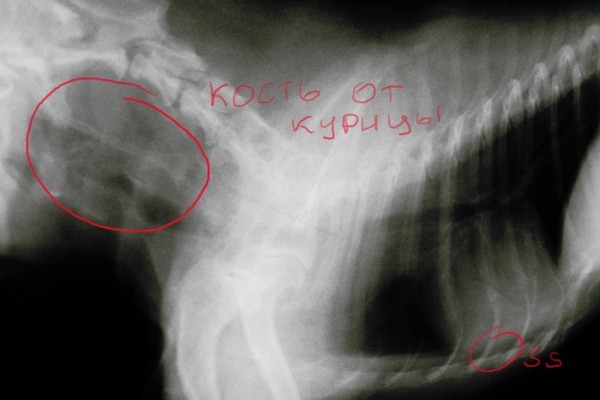

Показательные фотографии:

i-782.jpg

i-781.jpg

Пёсику повезло попал к хорошему доктору. Остался жив.